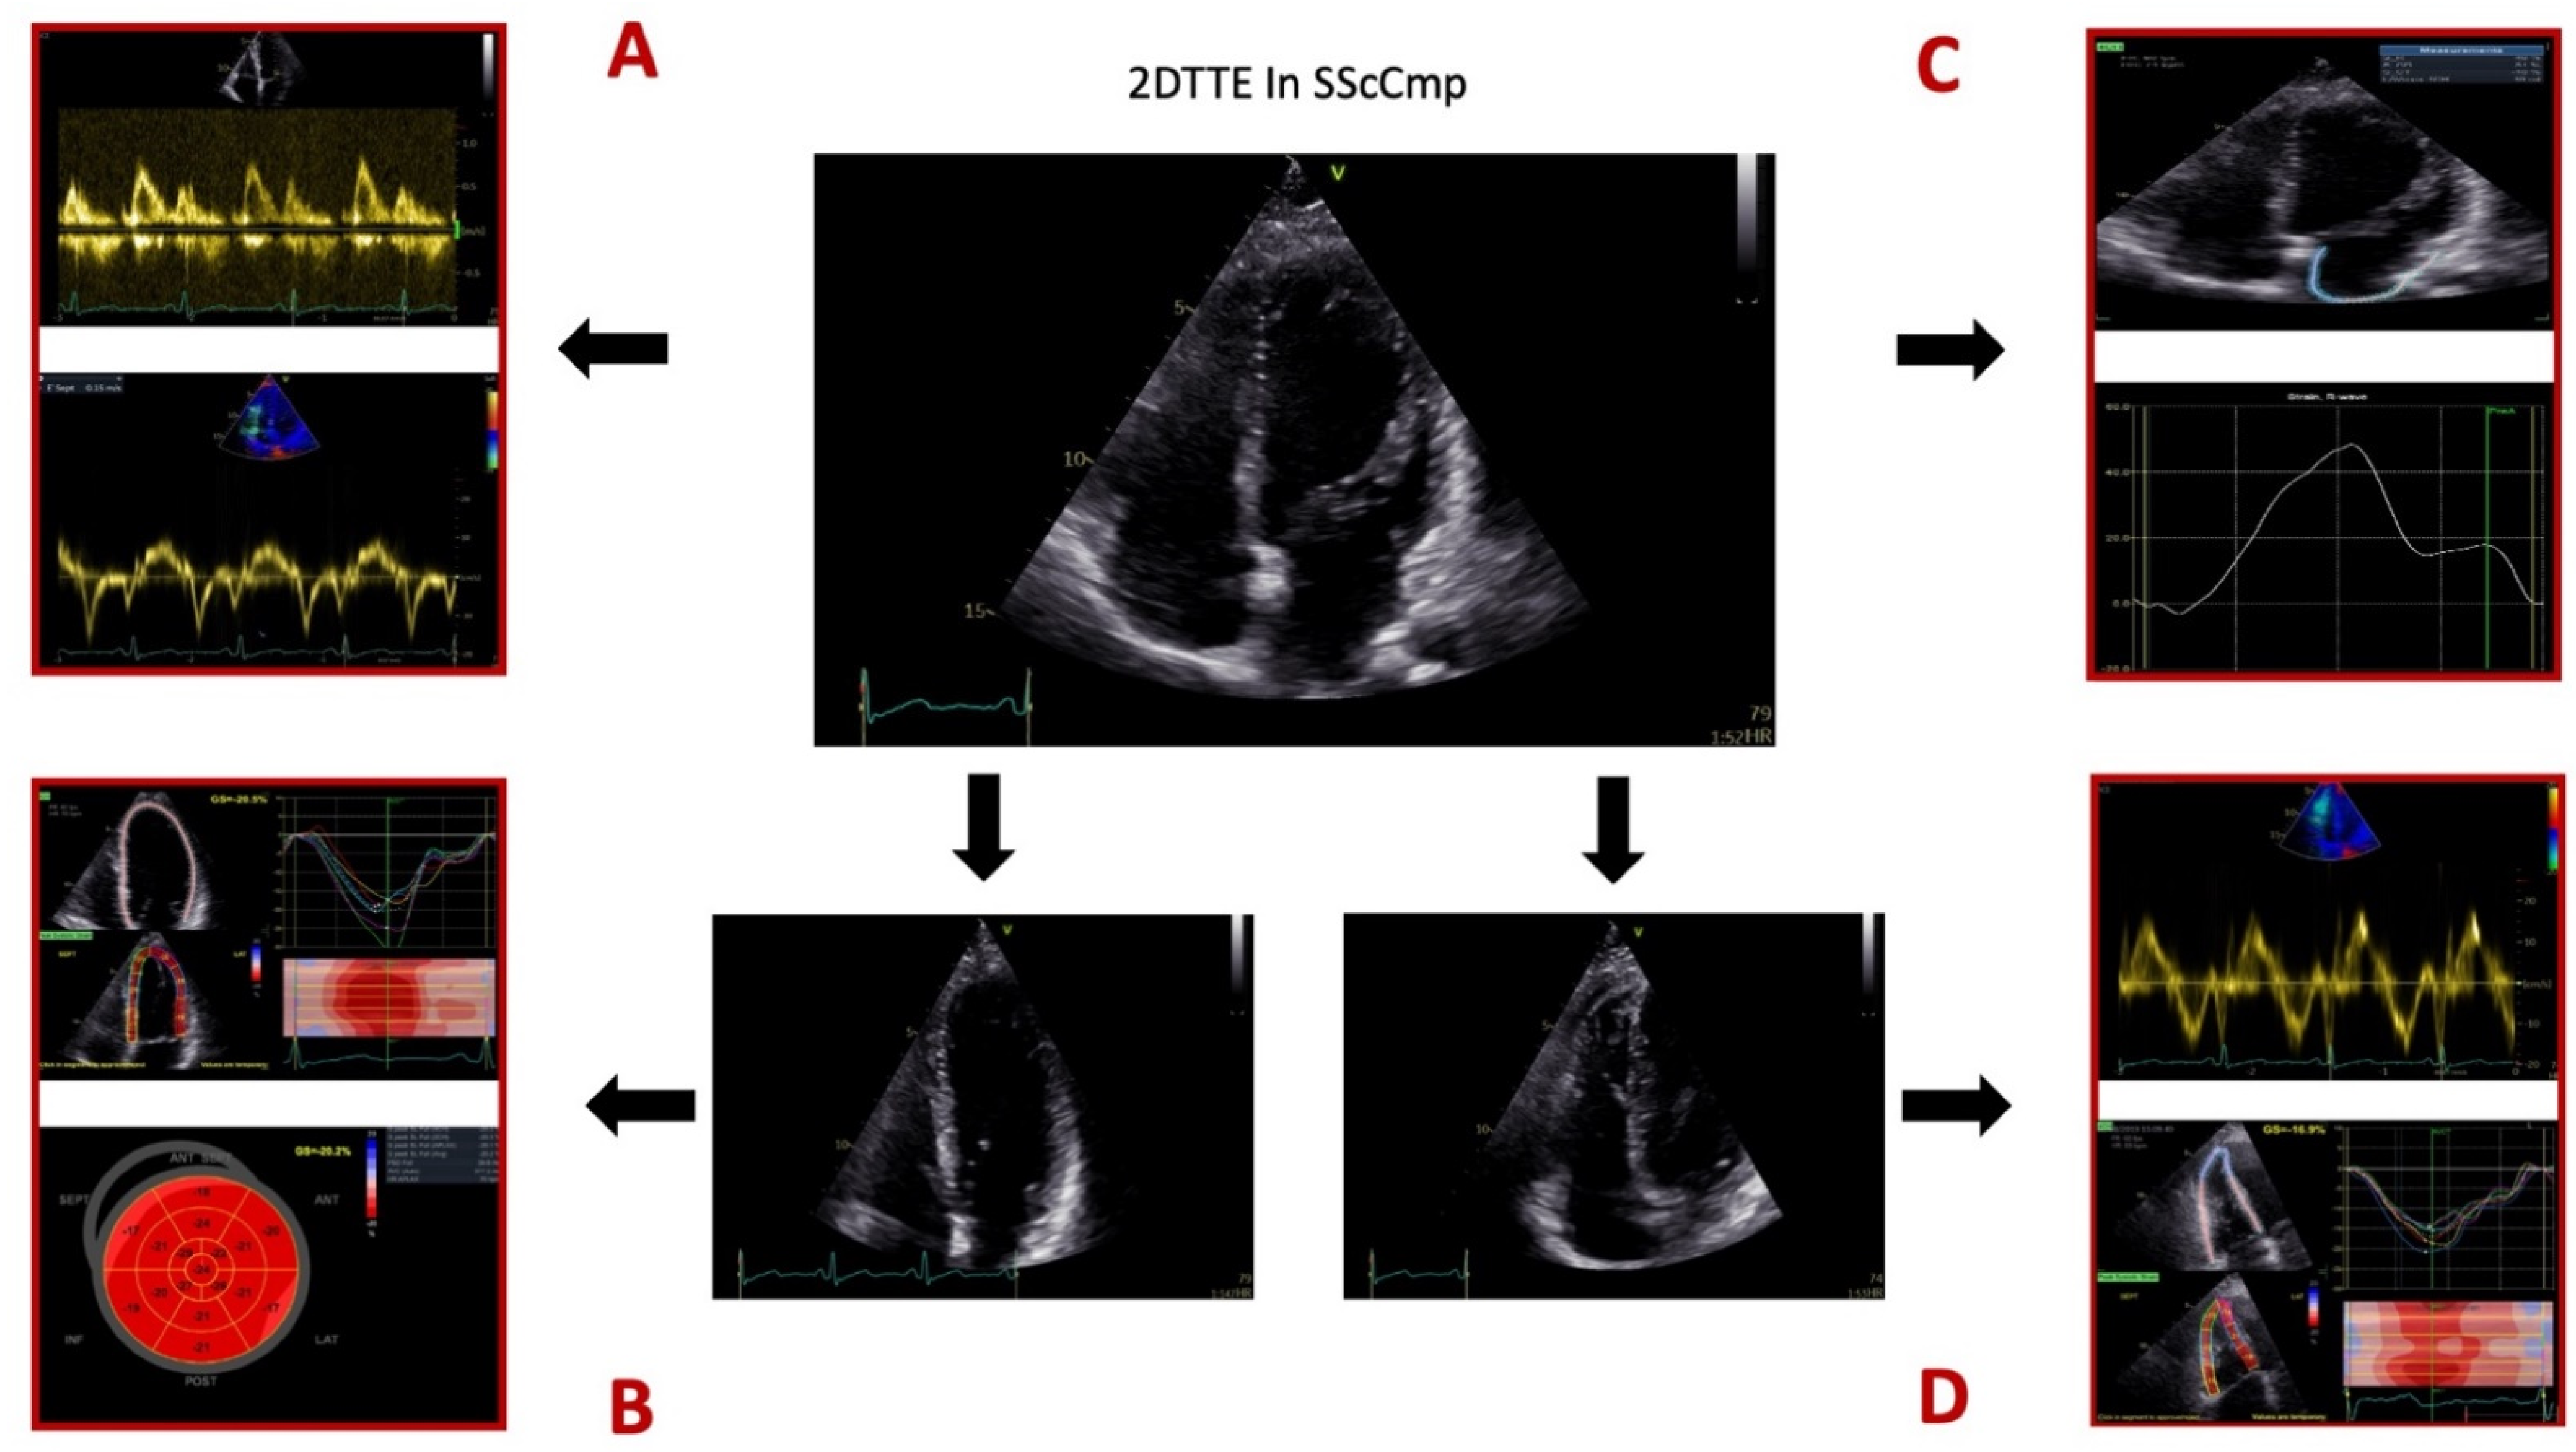

6.3. Echocardiographic Assessment of Primary Myocardial Disease in SSc

| .2DTTE | SSc patients need annual 2DTTE for assessing LV systolic and diastolic function and sPAP [51]. LV systolic function: 5.4% prevalence of LV systolic dysfunction [52]; reduced strain rate values in the IVS and antero-lateral wall [12]; myocardial electromechanical proprieties—diffuse deterioration of LV segments [3]. LV diastolic function: 4–5 times more frequent than systolic dysfunction (17–30% of cases) [22,53]; Risk factors for low e’velocities: duration of the disease, age, CAD, HTN [53]; e’-baseline value predicts mortality risk and every decrease in standard deviation elevates mortality risk 3.2 times [53]. VAC: Higher in dcSSc compared to lcSSc [51]; VAC might predict MACE in SSc population [51]. RV: Frequently involved in systemic diseases, either by direct injury, or because of associated PH [54]. Early dysfunction in SSc—associated with the degree of skin and pulmonary involvement and with anti-Scl70+ [12,54]. Early diastolic dysfunction [54]; prolongation of pre-ejection times [54]; RVFWS—significantly lower in SSc cases compared to healthy controls (irrespective of skin subtype or sPAP) [55]; apical and middle segments of RVFW—more damaged compared to the basal segment [55]. |